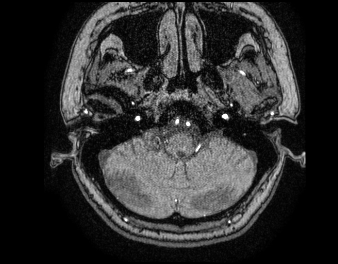

저는 소뇌위축증 환자이고요 유튜브에 오랜만에 찍은 mra를 공개할까 하는데요 제가 의사가 아니라서 소개할 부분이 명확치 않아서요 ㄷㄷ 여기서 소뇌가 제일 아래 잇는것 맞나요? 정상에 비하면 어디가 얼만큼 위축되어있나요?

• 1번 째 사진

• 안녕하세요. 채홍석 의사입니다. 우선 영상은 MRA 영상으로 뇌실질(소뇌도 포함됩니다)을 평가하기 위한 영상은 아닙니다.

소뇌위축증은 뇌척수액이 하얗게 보이는 영상에서 잘 보입니다. 제일 아래부분이 맞고 얼마나 위축되어 있는지 평가하기는 어렵습니다

올려주신 사진의 아래부분이 소뇌는 맞습니다. 다만 올려주신 사진은 MRA고 이는 혈관을 주로 보기위한 검사로 소뇌나 다른 대뇌의 이상여부를 판단하기에는 무리가 있습니다.

소뇌위축증으로 진단을 받으신 환자라면 위축이 있을테니 다른 MRI사진을 찾아서 올리는걸 추천드립니다.